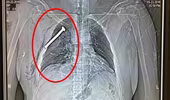

Rùng mình cảnh "bom đinh" tàn phá cơ thể nạn nhân vụ khủng bố ở Bỉ